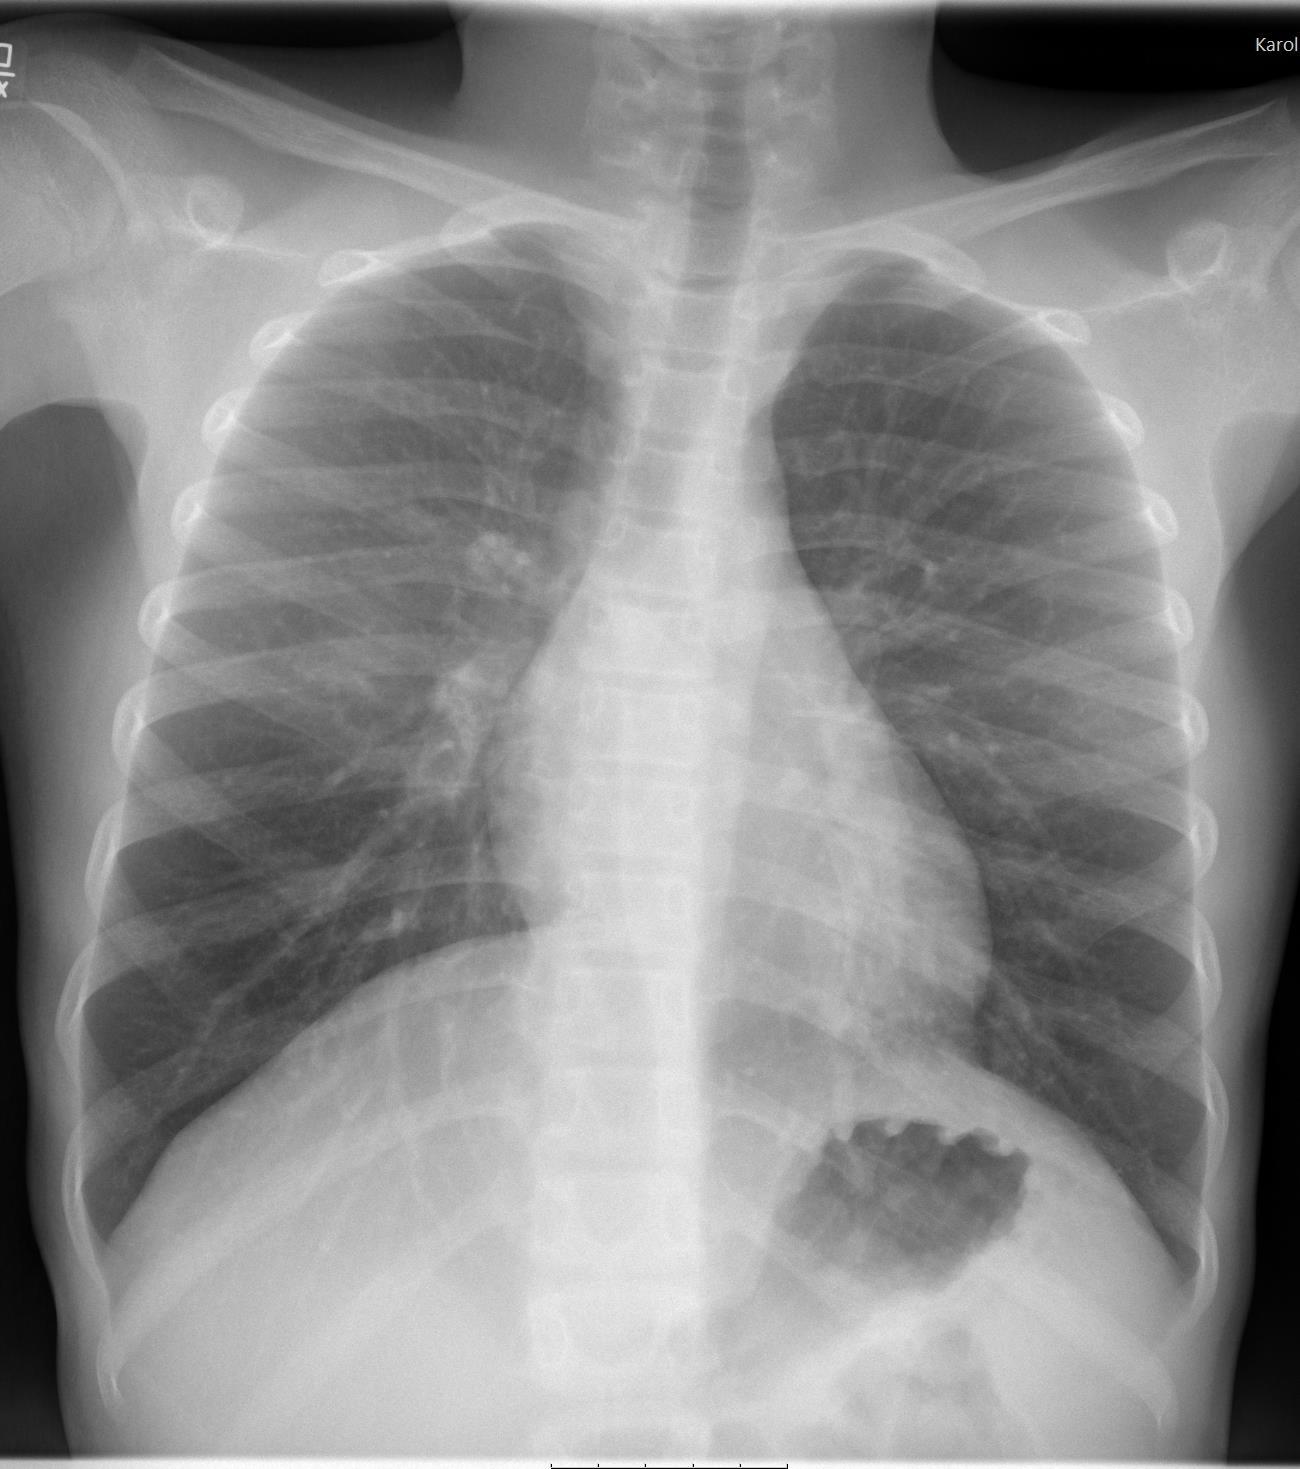

Imaging of Covid 19 infection in children CXR 9 C O V I D

Birmingham

Covid 19 CXR Imaging of Covid 19 infection in children